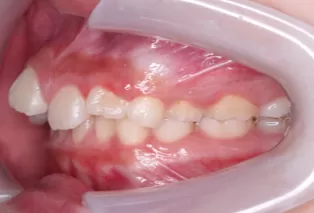

Photos intra-orales